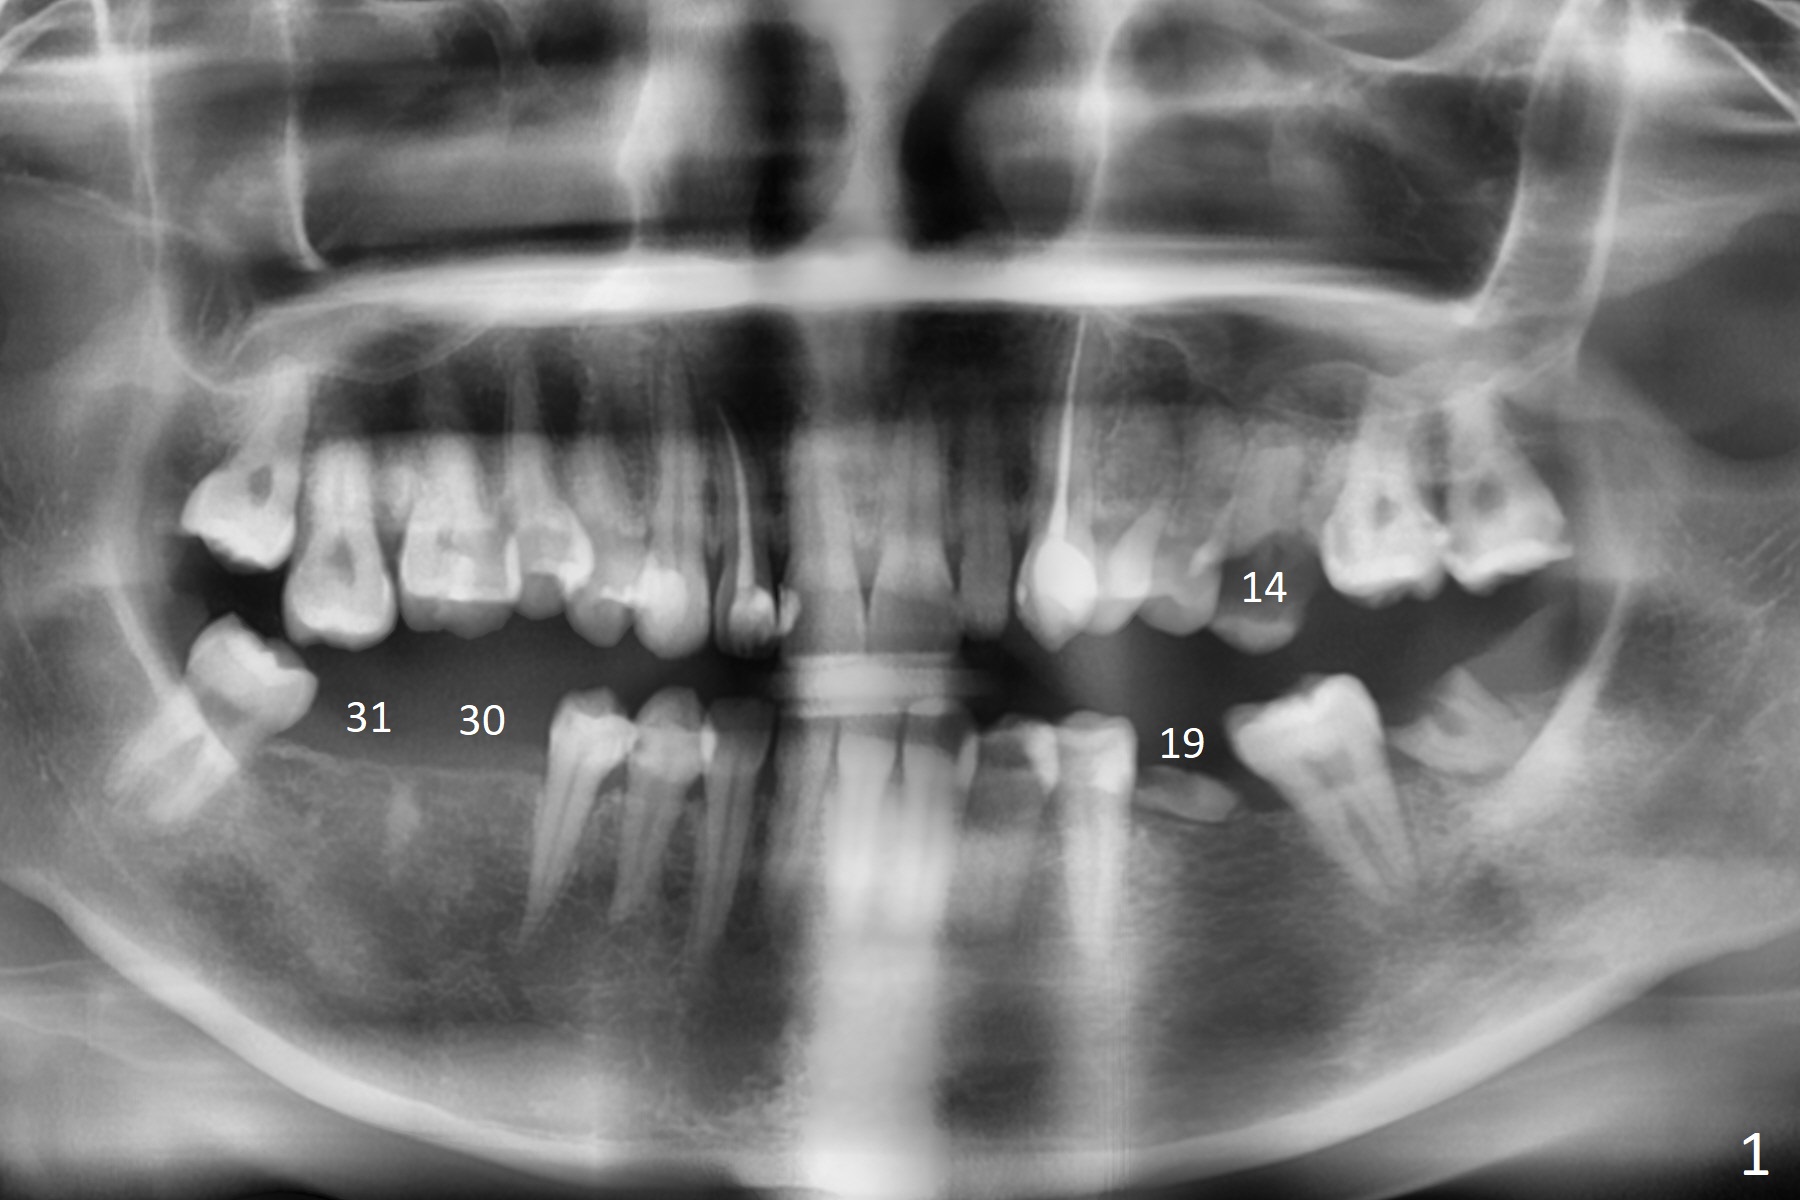

A 32-year-old woman has poor dentition: missing teeth and shifting (Fig.1). The teeth #14 and 19 will be extracted for implants (Fig.2,3 (5x8.5 and 4x11.5 mm)). Draw 2 tubes of blood for PRF. Prepare temporary and healing abutments for 14 and 19, respectively. SRP will be done with #17 extraction.